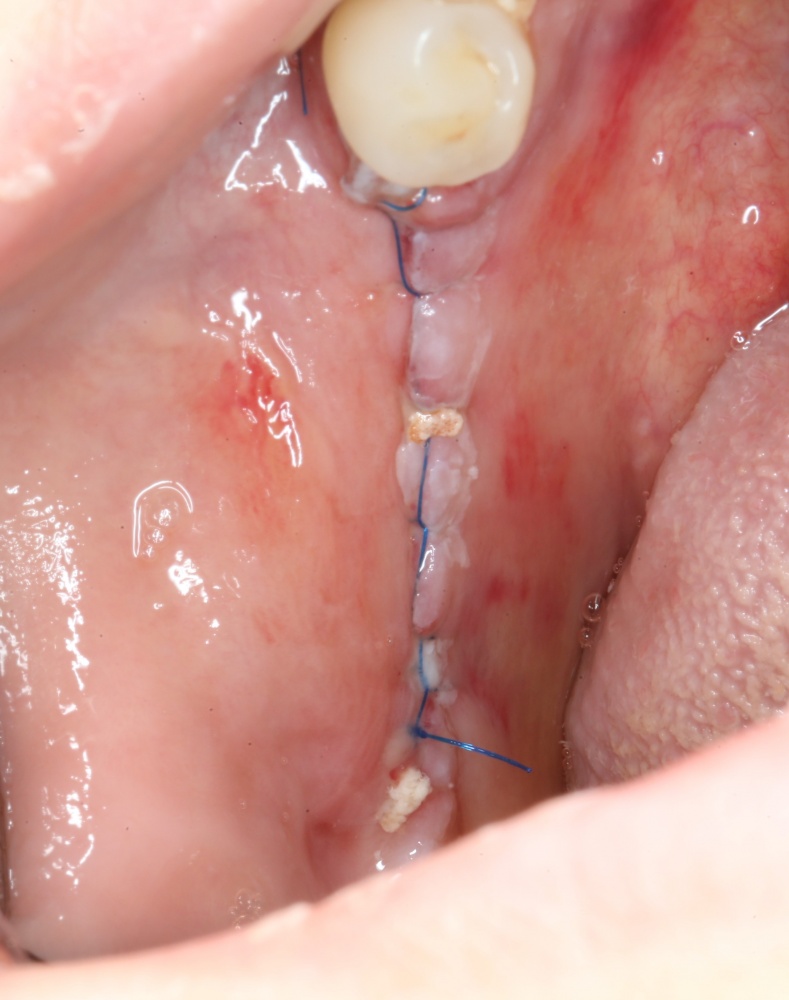

Наложение швов.

Если на этапе разреза и формирования раны всё сделано правильно, то наложение швов не вызывает особых трудностей. Периостотомия или послабляющие разрезы на периосте не требуются (ни практически никогда не требуются). А сами швы получаются аккуратными и герметичными:

Обрати внимание, что все шовные лигатуры находятся в пределах кератинизированной десны. Это позволяет избежать деформации тканей и лишних рубцов. В наиболее уязвимых местах (около зубов) шовные лигатуры лучше продублировать.

Если бы мне пришлось делать это сейчас, то я бы использовал непрерывный «матрацный» шов. Он удобнее, быстрее в наложении и комфортнее для пациента. Минус — если распускается, то распускается весь. К тому же, его очень неудобно снимать.

Несмотря на то, что уже тогда мы широко использовали непрерывные швы в подобных случаях, здесь я, во-первых, зассал (может распуститься), во-вторых, снятие швов предполагалось в поликлинике по месту жительства пациентки, и мне не хотелось, чтобы там при снятии швов начудили. Как выяснится позже — зря беспокоился.

Неизменно одно — в таких операциях мы использовали и до сих пор используем нерезорбируемые монофиламентные шовные материалы, поскольку они наиболее гигиеничные. Чтобы острые концы нитей не беспокоили пациента, их можно оплавить нагретой гладилкой или гуттаперчевым плаггером.